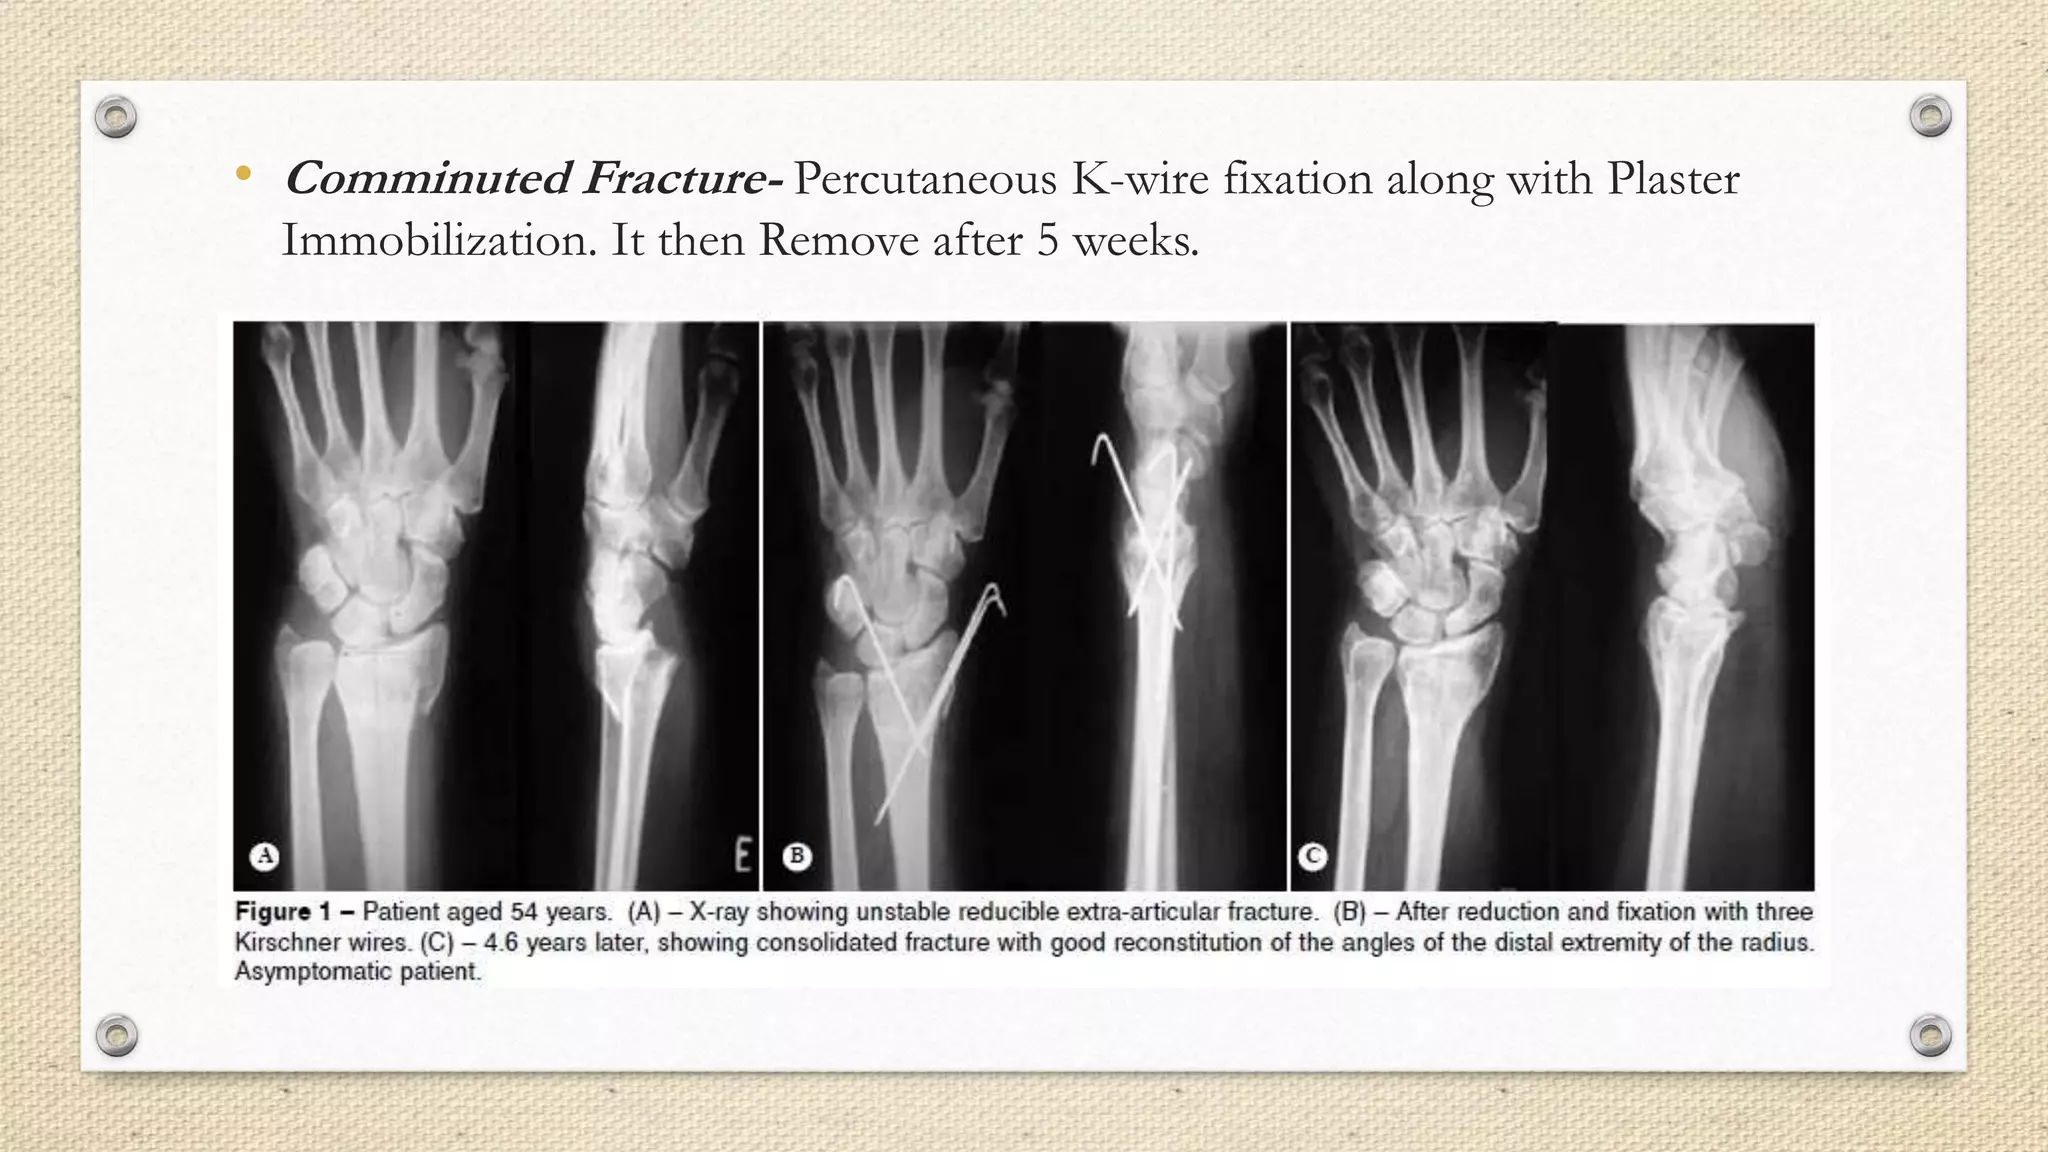

• Comminuted Fracture- Percutaneous K-wire fixation along with Plaster

Immobilization. It then Remove after 5 weeks.